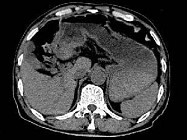

- 单项选择题根据所提供的图像,最可能的诊断是 ( )

A、胃淋巴瘤

B、胃平滑肌瘤

C、胃窦癌

D、胃窦炎

E、以上都不是